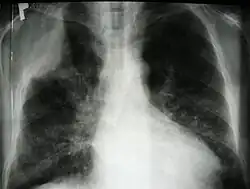

Guz Pancoasta (zespół Pancoasta, ang. Pancoast syndrome) – szczególna postać kliniczna raka oskrzela, zlokalizowanego obwodowo w okolicy szczytu płuca mogący naciekać żebra, kręgi, ścianę klatki piersiowej i struktury otworu górnego klatki piersiowej. Guz Pancoasta musi naciekać opłucną ścienną i wywoływać objawy neurologiczne, sama lokalizacja w szczycie płuca nie wystarcza do klasyfikacji nowotworu płuc jako guza Pancoasta[1]. Często dochodzi do uszkodzenia splotu ramiennego i zwoju gwiaździstego[1]. Stanowi około 5% przypadków raka płuc[2].

Około 70% guzów stanowi gruczolakorak, resztę stanowi rak drobnokomórkowy i olbrzymiokomórkowy[2]. Pierwszym objawem bywa stały ból okolicy barku, łopatki, a czasami także ramienia spowodowany uciskiem lub naciekaniem splotu ramiennego, opłucnej ściennej, żeber I-III; jest to ból charakterystyczny dla tej choroby[3]. Charakterystyczny jest zespół objawów neurologicznych spowodowanych uciskiem splotu barkowego oraz zespół Hornera (m.in. ptoza, mioza, enoftalmia) spowodowany uciskiem lub naciekaniem zwojów współczulnych. Guz Pancoasta z definicji jest zaawansowanym nowotworem (guzy T3 i T4 w klasyfikacji TNM)[2].